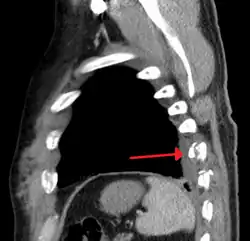

Plain X-rays often pick up displaced fractures but often miss undisplaced fractures.[13] CT scanning is generally able to pick up both types of fractures.[13]

Right sided pneumothorax and rib fractures -

Two broken ribs as seen on parasagittal CT